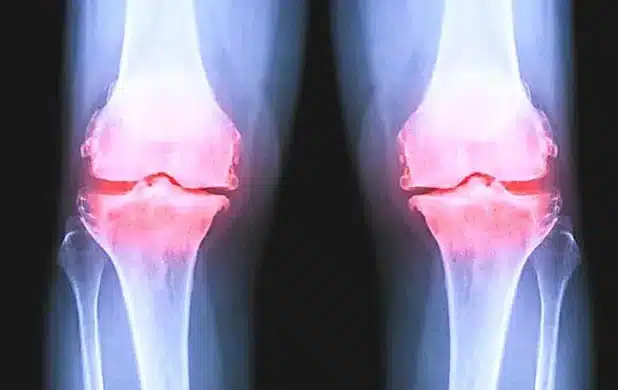

Nach Jahren schmerzhafter Gelenkabnutzung in meinen Knien, Händen und Hüften sowie dem Ausprobieren unzähliger „Lösungen“ weiß ich genau, wie zermürbend Arthrose sein kann.

Denn wenn man einmal unter Arthrose in den Knien, Händen oder Hüften leidet, möchte man alles dafür tun, um sich wieder normal bewegen zu können – ohne diese ständigen Schmerzen und die Steifheit …

Und genau diese chronischen Entzündungsprozesse und der Knorpelabbau in deinen Knien, Händen, Hüften oder anderen Gelenken sorgen dafür, dass die Beschwerden immer wieder zurückkehren – weil sich dein Körper in einem permanenten Zustand von Entzündung und Gelenkverschleiß befindet.

Am häufigsten tritt Arthrose in den Knien und Händen auf, gefolgt von Hüft- und Schulterarthrose.

Arthrose ist mehr als nur lokaler Gelenkschmerz – sie ist ein klares Signal dafür, dass sich dein Körper in einem chronischen Entzündungszustand befindet, der deine gesamte Gesundheit beeinträchtigt.

Sie ist das Ergebnis chronischer Entzündungsprozesse und von Knorpelabbau in Knien, Händen, Hüften oder anderen Gelenken – meist durch eine Kombination mehrerer sich gegenseitig verstärkender Faktoren.